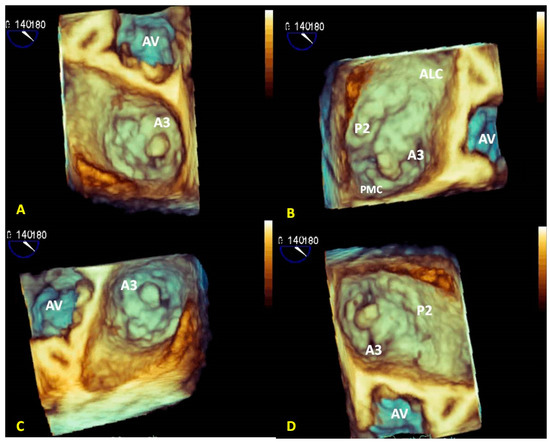

3.1. Anatomical Characterization